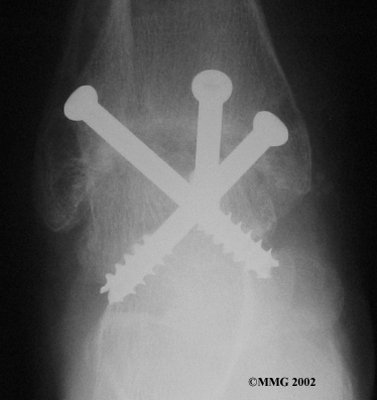

It is important when the surfaces are removed that the angles of the cut surfaces are correct. When the tibia is brought against the talus, the foot should be at a right angle to the lower leg. Once the cuts are made the bones must be held in place while they fuse. This can be done using large metal screws and metal plates if necessary. The screws are usually under the skin and are not removed unless they begin to rub and cause pain.

Inserting the screws

After ankle fusion, the physical therapists at Fyzical Provo can help you learn to walk smoothly and without a limp. Although time needed for recovery varies among patients, an ankle brace will typically replace your cast after eight to 12 weeks. Your surgeon will take X-rays frequently to see if the bones are fusing together. You will probably need to use crutches during the time you wear the cast. As the fusion grows stronger, you will begin to put more weight on your foot when walking.